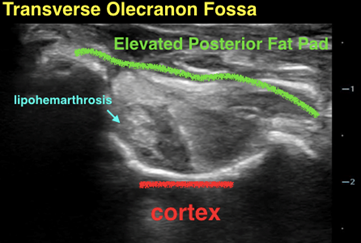

Position the elbow in a 90-degree, flexed position; this may also often be the position of comfort for the patient. Use a high frequency linear transducer for more superficial structures and higher resolution. Scan in both orthogonal planes as depicted below (longitudinal and transverse views). You are looking to identify any obvious cortical irregularity along the humeral cortex. Most importantly, you are evaluating for the presence of an effusion/lipohemarthrosis within the posterior aspect of the elbow joint, which results in an elevation and displacement of the posterior fat pad.

In the elbow with an occult supracondylar fracture, the posterior fat pad will be elevated above the bony prominences in both orthogonal planes

- Scan the elbow in both orthogonal planes looking for elevation of the posterior fat pad above the curvature of bony prominences.